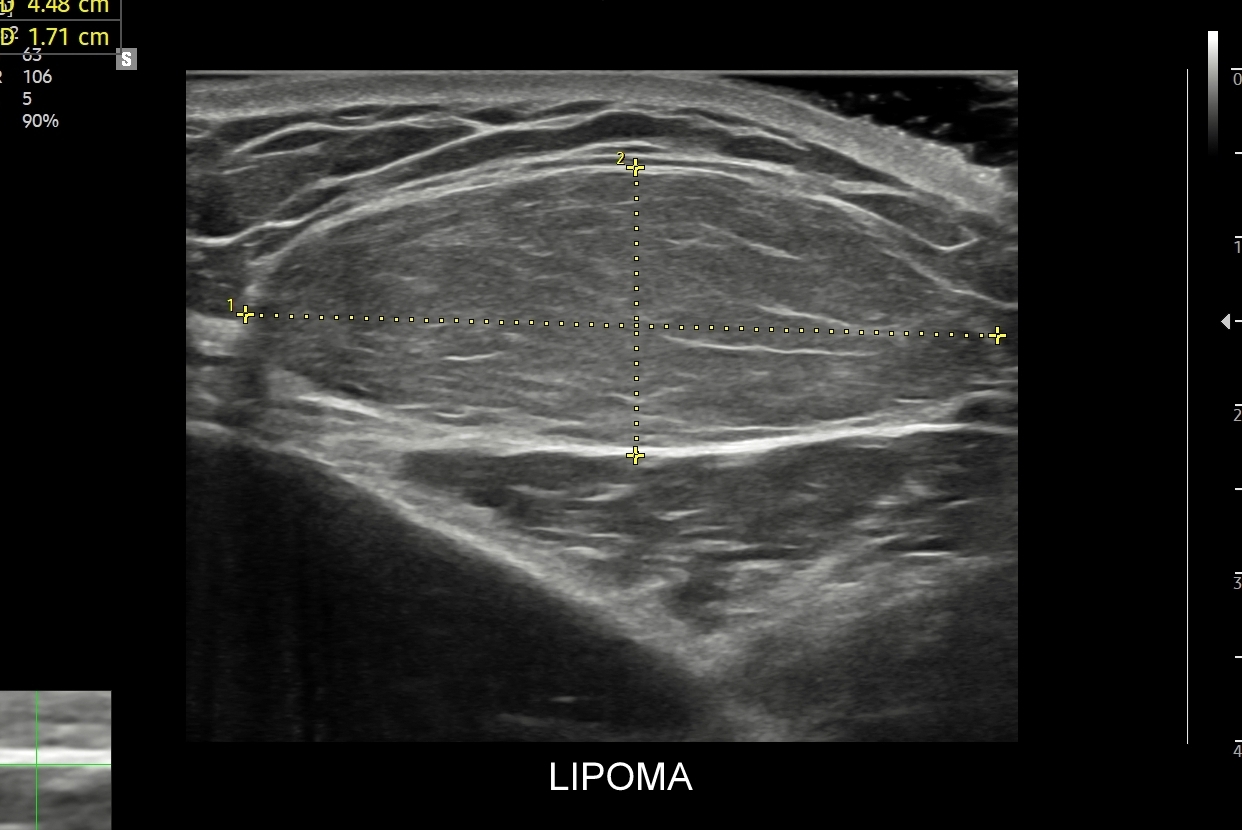

Badanie USG skóry i powłok jest metodą diagnostyczną, która swoją czułością oraz dokładnością przewyższa w ocenie patologii powłok badanie rezonansem magnetycznym. W obrębie powłok ciała w badaniu USG najczęściej rozpoznaje się różnorodne guzy oraz stany zapalne. Wśród guzów dominują łagodne tłuszczaki, kaszaki i torbiele inkluzyjne, a także przepukliny. U młodszych pacjentów często wykrywa się naczyniaki. Rzadziej spotkane są guzy złośliwe jak mięsaki, czy przerzuty nowotworowe. W pracowni USG dr Szczepańskiego poza wizualną oceną guzów powłok przeprowadzana jest ich ocena biologii w kontekście cech złośliwości i oceny przewidywalnego tempa wzrostu.

USG tkanek miękkich obejmuje ocenę diagnostyczną opisanych już wcześniej patologii, ale także zmian miękkotkankowych położonych w głębszych warstwach powłok oraz obszarach podpowięziowych takich jak chrząstki, ciała tłuszczowe, mięśnie, ścięgna, troczki, pochewki ścięgniste, stawy i gangliony, torbiele wrodzone, czy aparat paznokciowy.

Najistotniejszą grupą chorób tkanek miękkich są nowotwory złośliwe wywodzące się z tkanki łącznej, czyli mięsaki. Występują one częściej młodych i zdrowych dotąd dorosłych, częściej u kobiet, a objawiają się zwykle w sposób podobny do łagodnych schorzeń takich jak przepukliny, czy tłuszczaki. Badanie USG pozwala na szybie rozpoznanie mięsaka i wdrożenie szybkiej ścieżki leczenia.